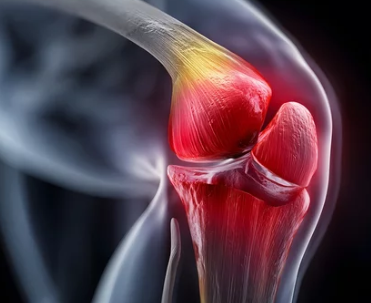

퇴행성관절염은 나이가 들면서 관절 연골이 점차 닳아 없어지고, 뼈와 뼈가 맞닿으면서 통증과 염증이 생기는 대표적인 만성 질환입니다. 단순한 관절 통증으로 여겨 방치할 경우, 일상생활의 질이 급격히 떨어질 수 있습니다.

- 충격을 흡수하던 연골이 손상되면서 뼈끼리 직접 부딪히고 마찰

- 주로 무릎, 손가락, 고관절, 척추 등에 발생